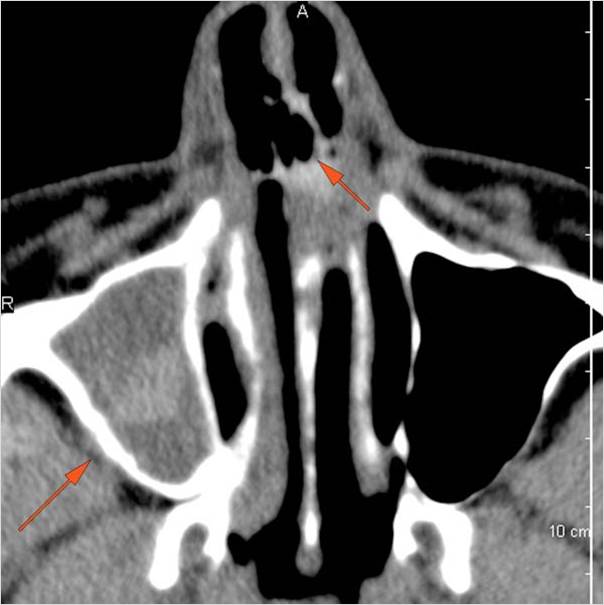

Sinuses

There is soft tissue swelling anterior to the frontal sinus or in the soft tissues surrounding the maxillary sinuses.

There is mucoperiosteal thickening in the sinuses.

There is mucosal enhancement in the sinuses.

There is bone erosion along the walls of any affected sinuses.

There is an appearance of bone expansion, due to regressive remodeling and suggestive of pre-existing mucocele, along the walls of any affected sinuses.